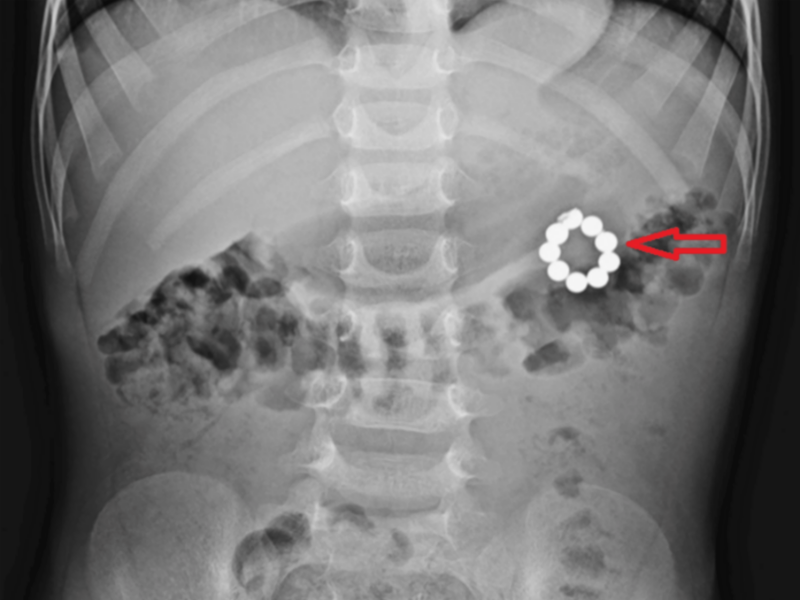

| 국제 학술지 '큐레우스'에 공개된 구슬 자석을 삼켜 응급 개복 수술을 받은 5세 남아의 복부 엑스레이 사진. /사진=큐레우스 |

의료진에 따르면 남아는 3일간 지속된 복통과 메스꺼움으로 병원을 찾은 것으로 전해졌다. 복부 엑스레이 촬영 결과 아이의 뱃속에 여러 개의 구슬이 연결된 모양의 이물질이 관찰됐다.

의료진은 내시경으로 위 안의 구슬 5개를 꺼냈으나, 나머지 4개를 제거하지 못해 응급 개복술을 시행했다. 개복 결과 위와 대장을 잇는 비정상 통로인 '위결장 누공'이 형성돼 있었고, 유착된 조직을 박리하자 누공 안에서 지름 4㎜ 크기의 자석들이 확인됐다.